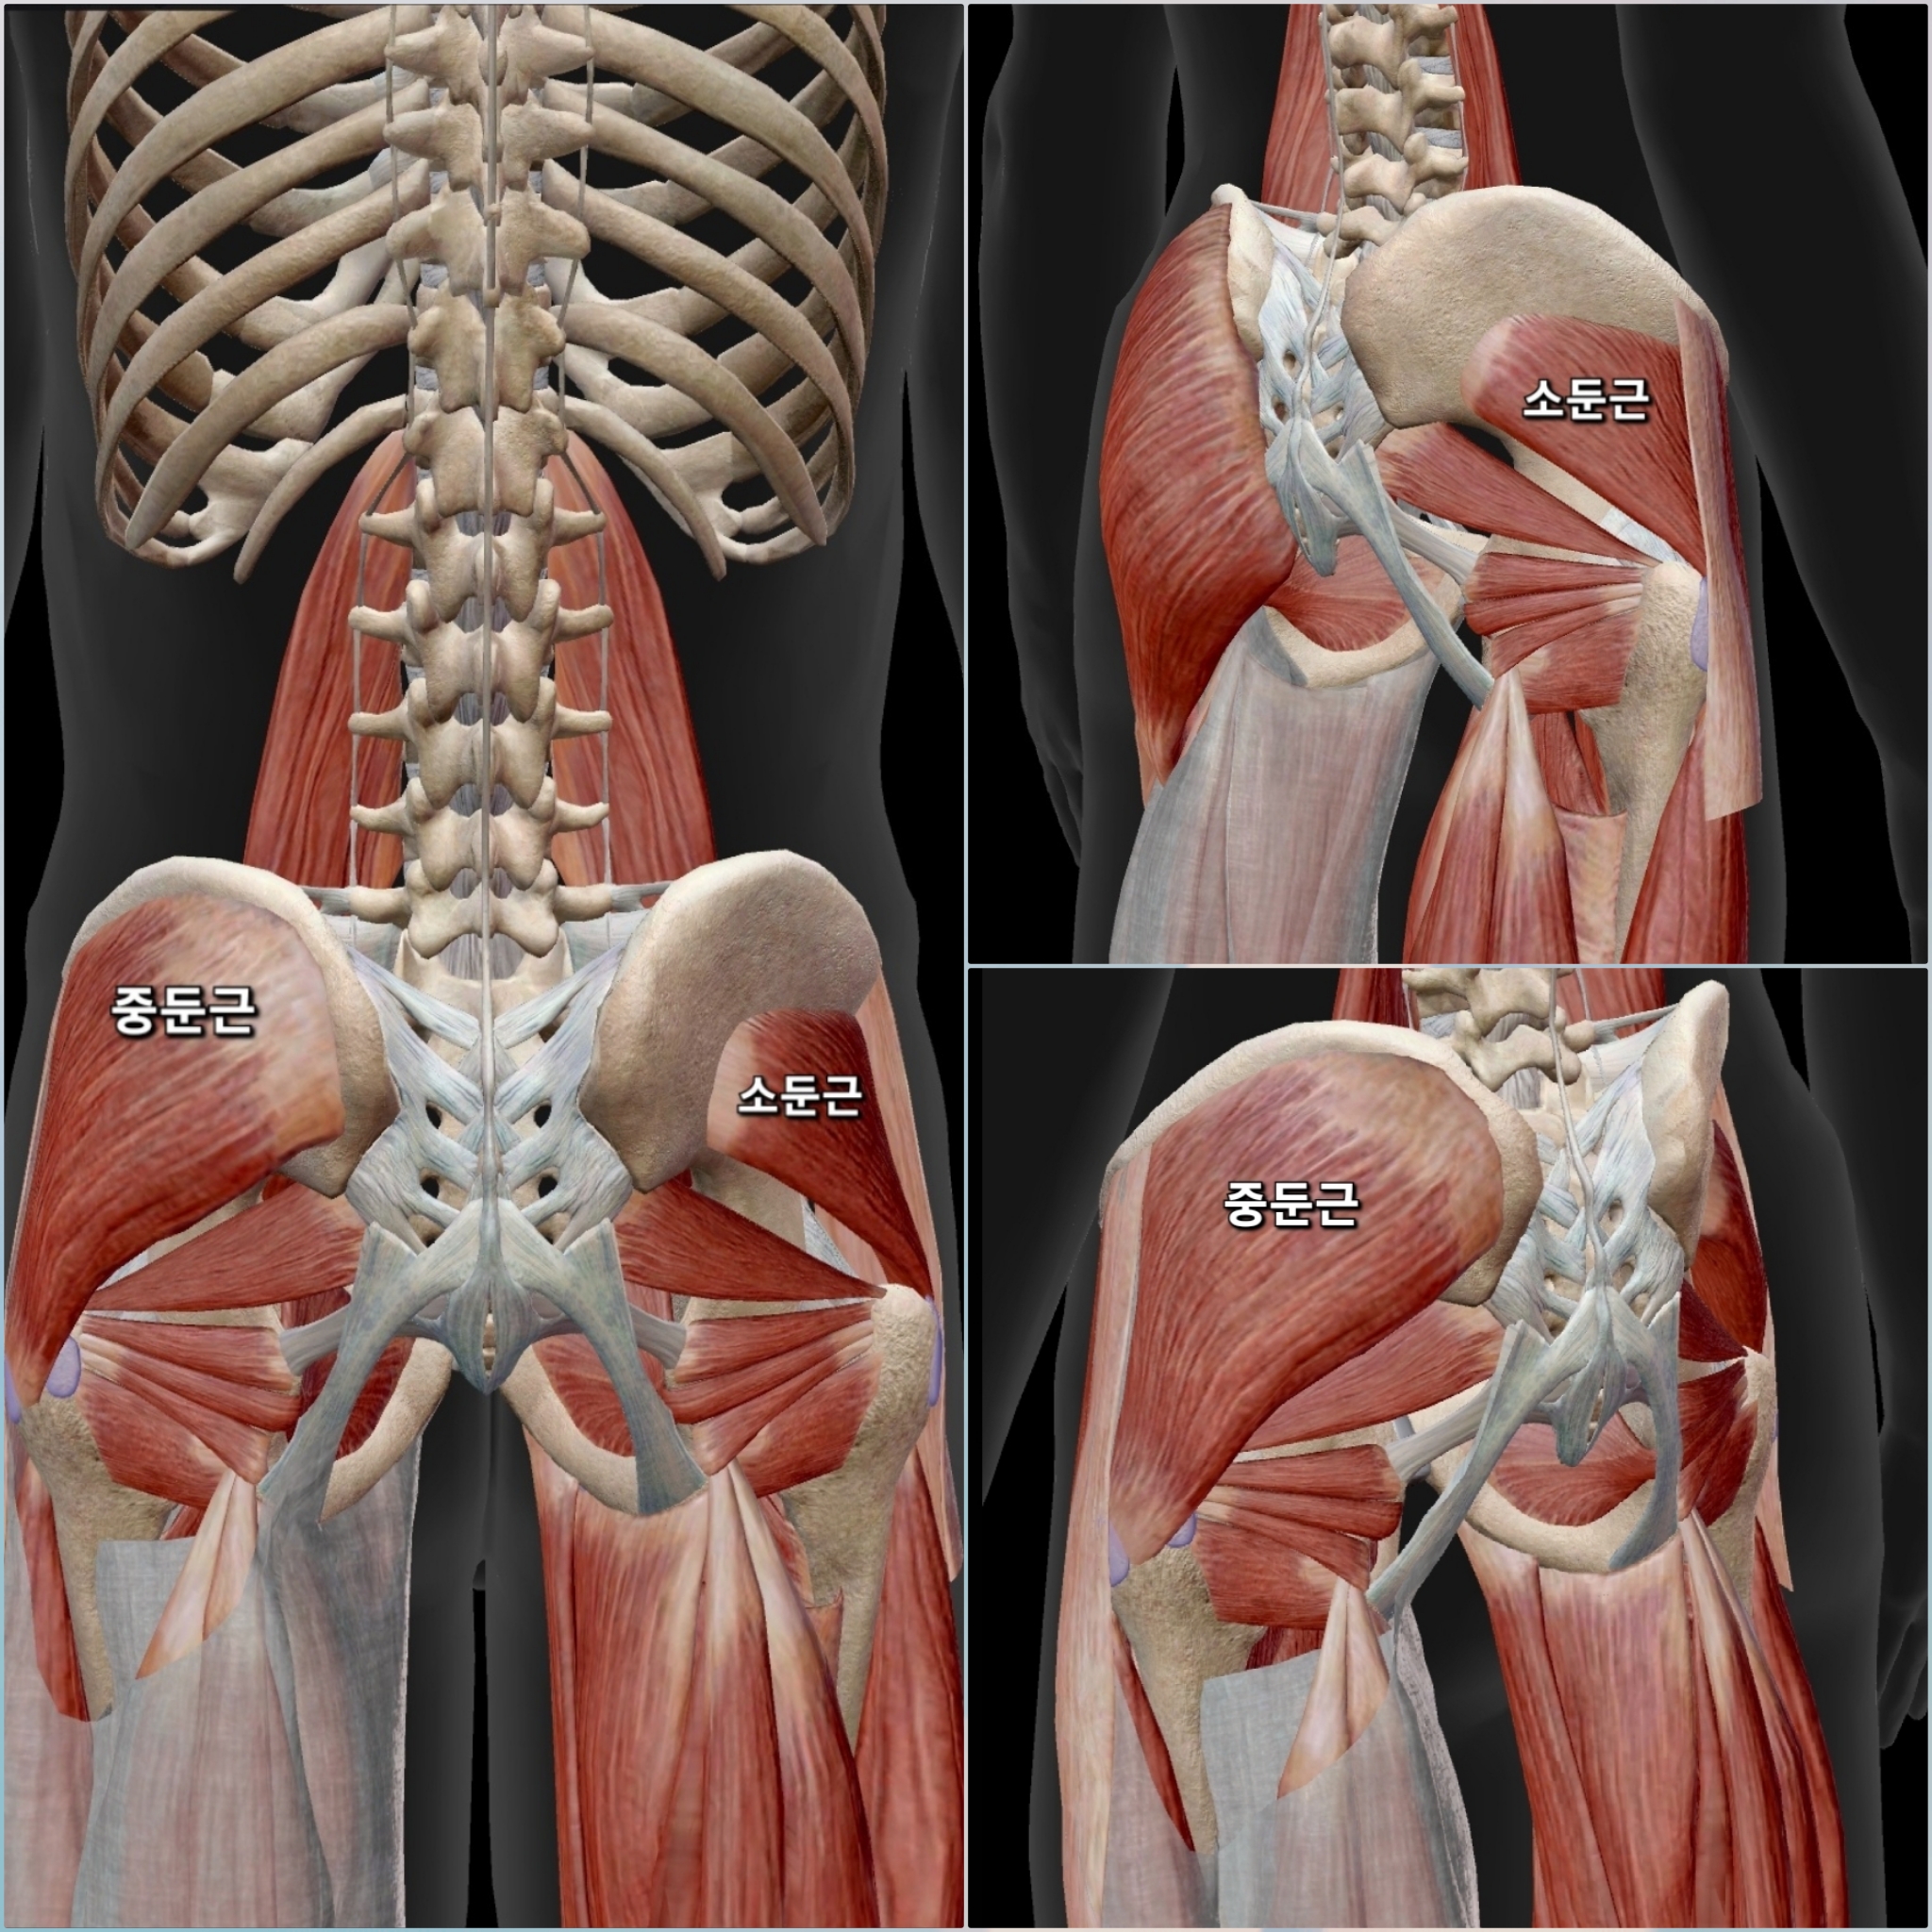

엉덩이 바깥쪽통증 (고관절 옆, 대퇴부 측면통증)

양반다리시 고관절이 안으로 말리면서 충돌(FAI)이 주로 앞쪽(사타구니)에서 발생하지만 다른 원인으로 엉덩이 바깥쪽으로 통증을 호소하기도 합니다

이유 : 중둔근, 소둔근 등의 근육이 약하거나 긴장돼서

ㆍ중둔근은 원래 다리를 바깥쪽으로 유지해 주는 역할을 하는데 중둔근의 약화로 고관절이 안쪽으로 말리면(내회전 되면) 중둔근이 늘어난 상태로 버티느라고 과부하가 걸려서 통증이 생길 수 있습니다 즉 중둔근이 "내가 버틸 힘이 부족한데 억지로 버티려고 하다 보니 뻐근하고 아프다!"라고 신호를 보낸다고 쉽게 생각하면 됩니다

ㆍ원래 중둔근이 고관절을 바르게 유지해야 하는데, 약해지면 허벅지 바깥쪽(TFL, 장경인대)이나 엉덩이 근육(대둔근)이 대신 부담을 떠안아 힘을 쓰게 됩니다 이렇게 보조근들이 보상작용이 계속되면서 엉덩이 바깥쪽 근육들이 경직되고 근육들이 뻣뻣해져서 추가적인 통증이 생길 수 있습니다

관련 문제 : 고관절 충돌 증후군 / 점액낭염

ㆍ 고관절이 안쪽으로 돌아가면 허벅지 뼈(대퇴골)의 바깥쪽 돌출 부위(대전자, Greater Trochanter)가 엉덩이 근육과 부딪히면서 고관절 충돌 증후군으로 염증이 생길 수 있습니다 이걸 대전자 점액낭염(트로찬테릭 버사, Trochanteric Bursitis)이라고 하고, 중둔근·소둔근과 관련된 통증을 유발합니다